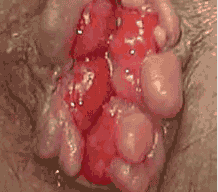

痔疮肉芽即为痔疮脱出,是内痔和混合痔的主要症状之一,指在大便过程中肛门处有小肉球突出来。痔疮脱出不仅会加重痔疮疾病,而且还对生活有很严重的影响。

洛阳东大肛肠医院医师指出:痔疮痔核早期的脱出能自行回纳,中期的脱出需要用手回纳,后期的脱出不能回纳,且痔核有被嵌顿的可能。如果这个时候还不及时的治疗,就会引起走路,咳嗽等都会脱出,十分严重。